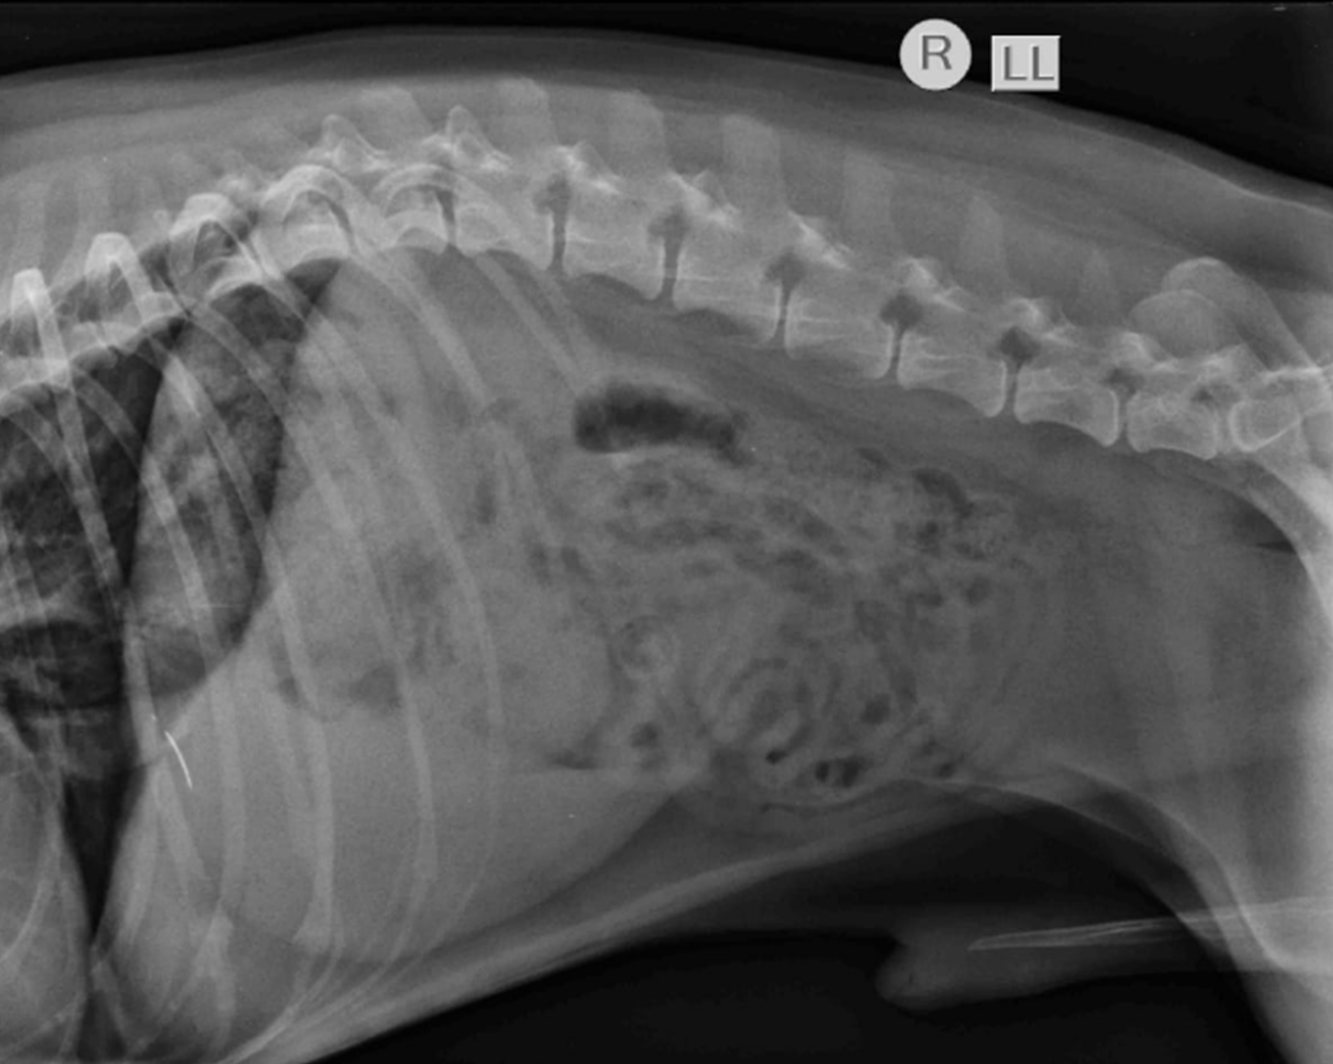

RX Estrechez de los espacios T12-T13 y T13-L1. Discopatias mineralizadas con extrusión de material discal en los espacios L1-L2 y L2-L3.

En 24 hs quedó paralítico, miembros posteriores extendidos hacia craneal. Retención de orina, no defeca. Alerta, come bien.